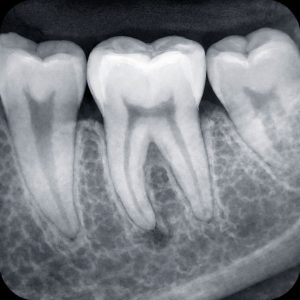

Dentalni radiogram

retroalveolarni snimak

Fleksibilni VSP senzori u 4 različite veličine će Vas iznenaditi visokim kvalitetom dobijene slike.